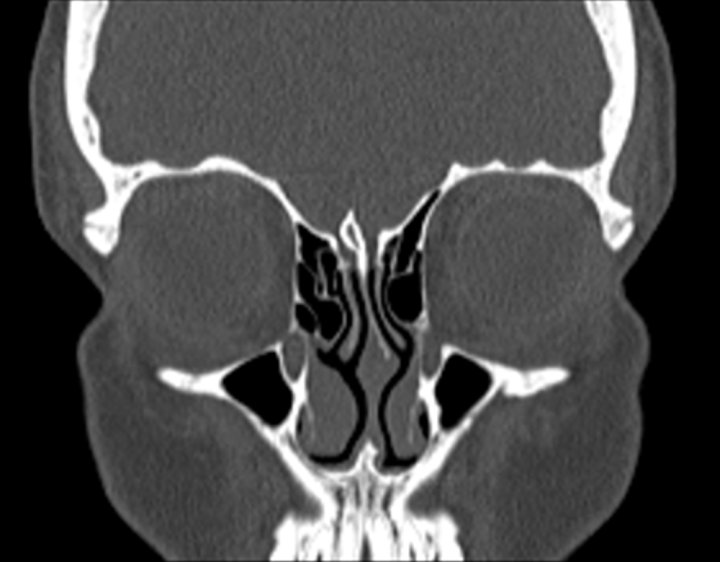

Click any image for labels.